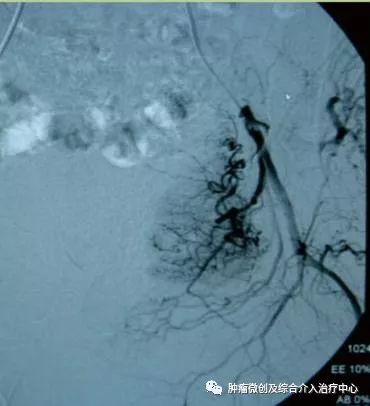

(术前DSA造影提示肠系下动脉增粗、增多、絮乱,临床表现为便血,系破裂出血)